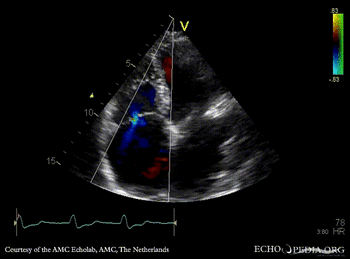

PLAX: dilated coronary sinus A4CH with Color Doppler: severe tricuspid regurgitation